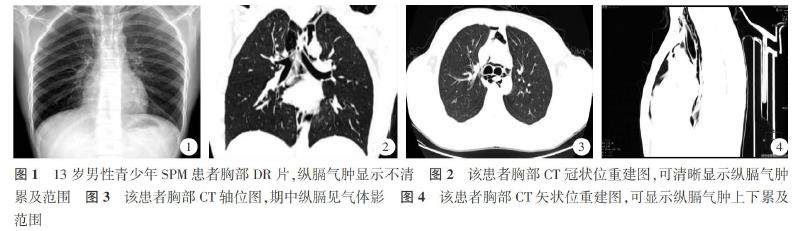

【Abstract】Objective To investigate the imaging findingsand clinical analysis of spontaneous pneumomediastinum(SPM)inadolescents.MethodsAretrospective analysis was conductedon 31clinicallydiagnosed adolescent patients with SPMas the research subjects.All patients underwent digital radiography (DR)or/and multi-slice spiral CTimaging,with afocus onanalyzing the imaging resultsand clinical characteristics of thepatients.ResultsAll 31 patients with confirmedadolescent SPM in this group underwent multi-slice spiral CT examination.25 patients (81%) (2号 underwent chest DR within 24 hours before undergoing CT examination.TheDRresults showed that1O of the 25 patients had a cleardiagnosis,6 had a suspected diagnosis,and9had no obvious positive signs.Allcases were confirmed by CT.The onset of the disease in the patients in our research group was triggered by exercise,coughing, vomiting,and emotional agitation.Thesymptomsof thepatients included chestpain,chest tightness,asthma,discomfortin theneckand chest,discomfort inswallowing,and pain.Allpatients recoveredafterconservative treatment. ConclusionThe clinical manifestations of SPMinadolescents are notparticularlydistinctive.Multi-slice spiral CT examination can provideadefinitive diagnosis,and in the absence of complications,most casescan be treated conservatively and recover fully.